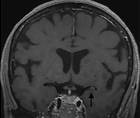

Stroke Snapshot: Intracranial MRI Vessel-Wall Imaging

Mitchell Barnes, DO; Parham Moftakhar, MDMitchell Barnes, DO; Parham Moftakhar, MD